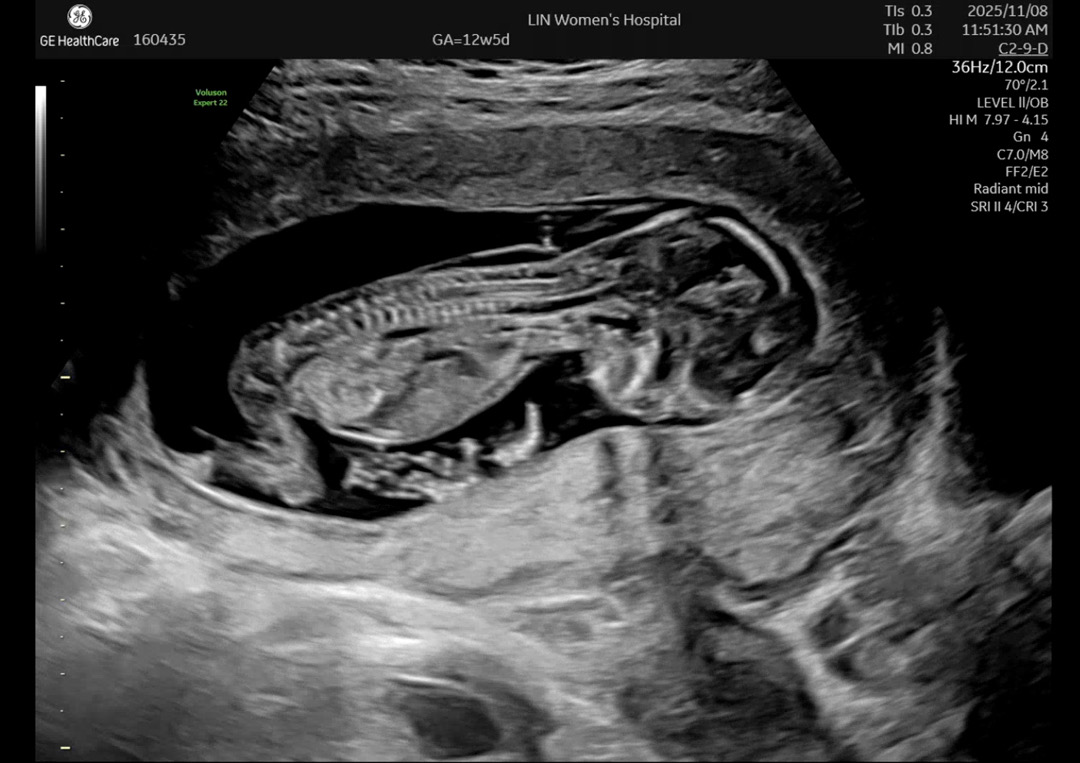

12주 5일 각도법 봐주세요!!! 제발...💚

보시기에 어떤가요? 😳 전.. 여러 글을 봐도 전혀 모르겠어서 ㅜㅜ